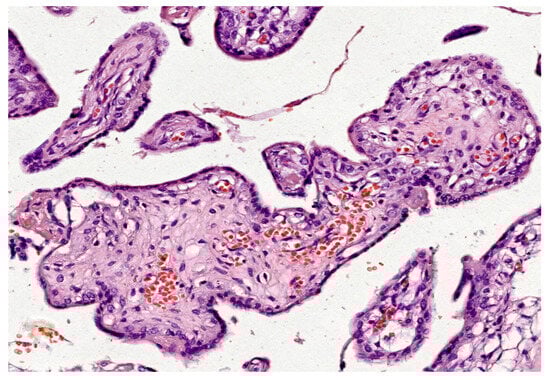

| Gestational Trophoblastic Diseases [127] | - Implicated in abnormal trophoblast proliferation and differentiation - Alters angiogenesis | - Hydropic swelling of villi - Trophoblast hyperplasia - Abnormal vasculature |